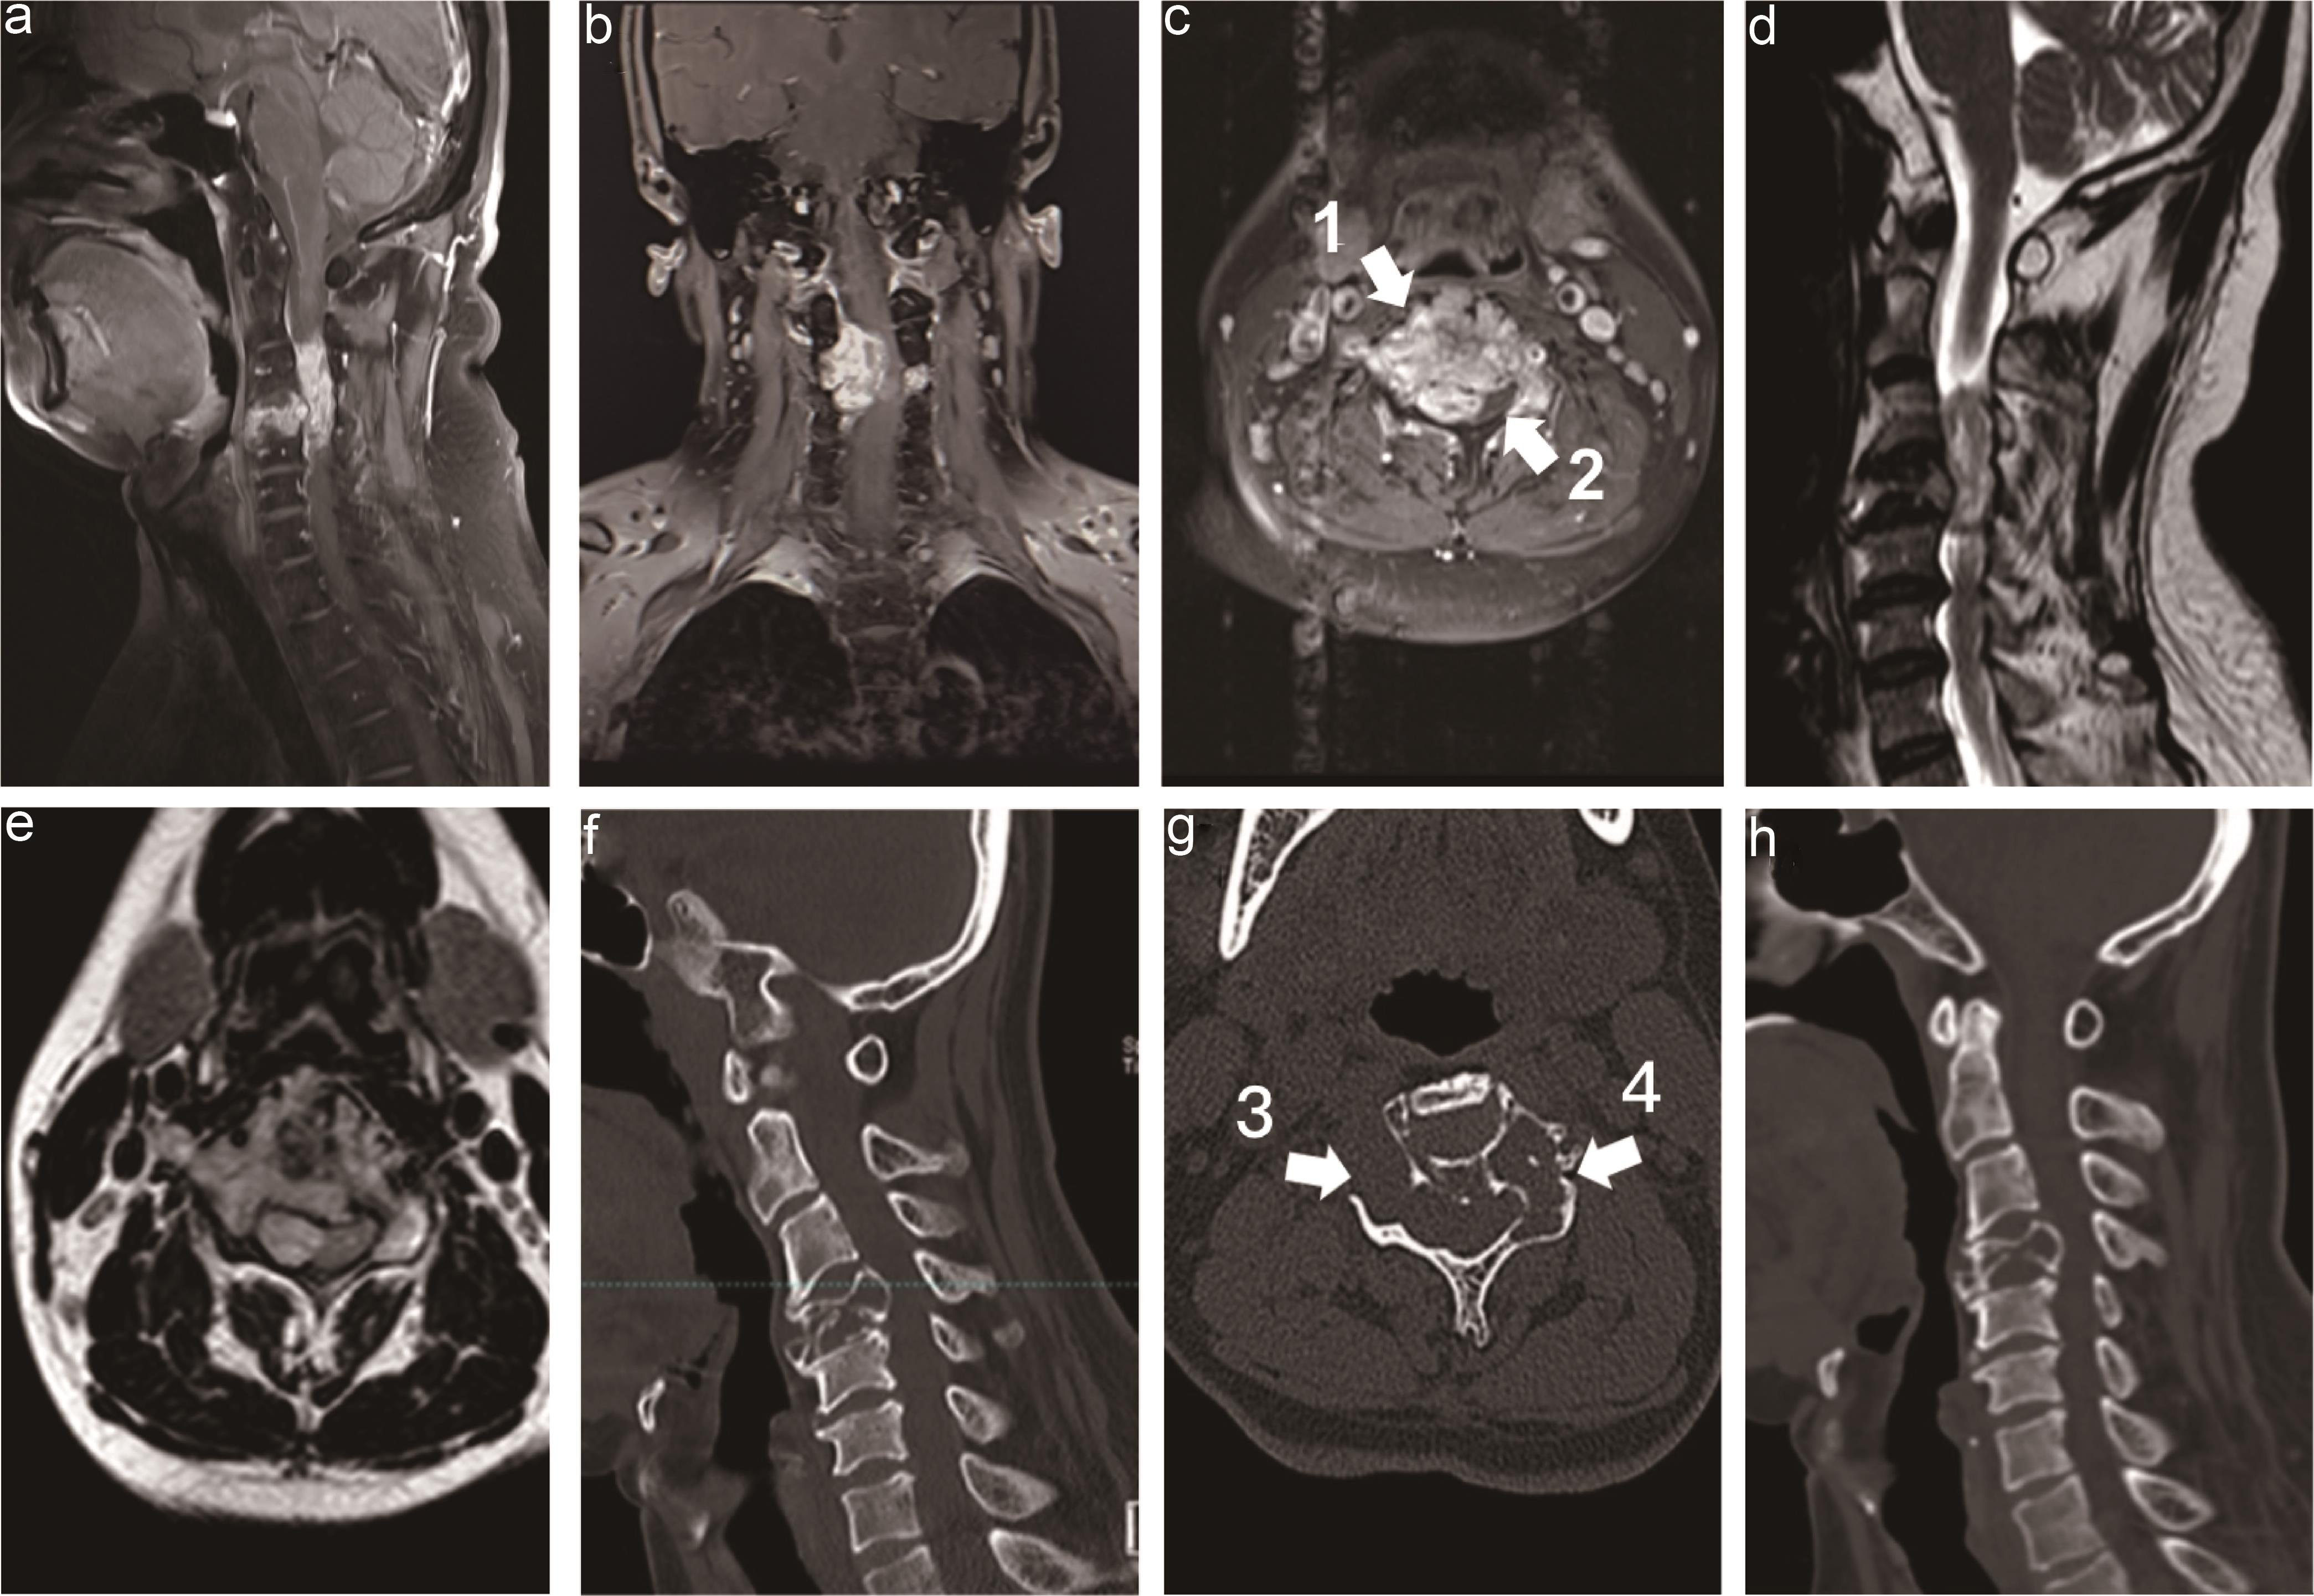

The postoperative course was uneventful, and the patient’s limb weakness gradually improved. One year after surgery, the patient could walk and write independently, with strength regained to 4/5 in the upper extremities and 5/5 in the lower extremities. The modified Japanese Orthopedic Association score improved to 15 out of 17 points. A review of cervical MRI (Fig. 3a and b) one year postoperatively showed no tumor recurrence. CT (Fig. 3c) demonstrated good fusion of the vertebral bodies, and X-ray films (Fig. 3d) showed stable fixation materials without loosening or displacement. Currently, the patient’s bowel function has improved; however, he still requires assistance with defecation in bed.

Fig. 3  Follow-up MRI, CT, and X-ray 12 months after surgery.

The sagittal T2WI (a) and enhanced T1WI (b) MRI revealed that the tumor was removed totally, and there was no recurrent tumor. CT (c) demonstrated good fusion of the vertebral bodies, and X-ray films (d) showed stable fixation of materials without loosening or displacement. CT, computed tomography; MRI, magnetic resonance image; T1WI, T1-weighted image; T2WI, T2-weighted image.